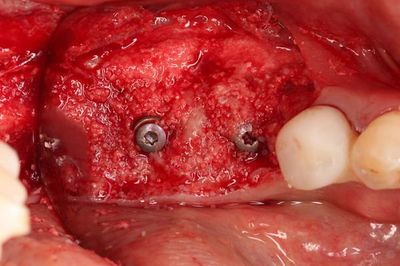

無事に2本のインプラントの埋入を終えました。

トランスファージグを取り外しました。

ヒーリングスクリューH0.5mmでスクリューホールを保護します。